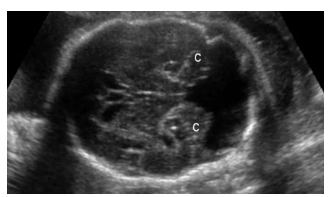

Ao realizar o exame ecográfico obstétrico de uma gestante 37 semanas, você se depara com a seguinte imagem. Assinale a alternativa correta.

A

Malformação de Chiari I.

B

Malformação de Chiari II.

C

Hidranencefalia.

D

Malformação de Dandy Walker.